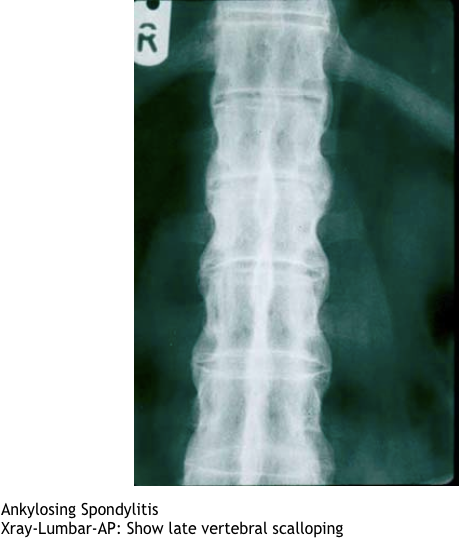

What imaging is useful in dx ank spon?